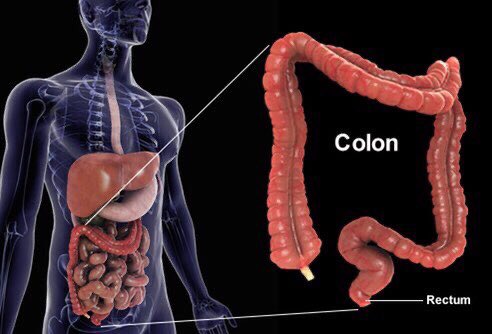

العلاقة بين #القولون_العصبي والمشاكل والأمراض النفسية علاقة مهمة ووطيدة

العلاقة بين #القولون_العصبي والمشاكل والأمراض النفسية علاقة مهمة ووطيدة